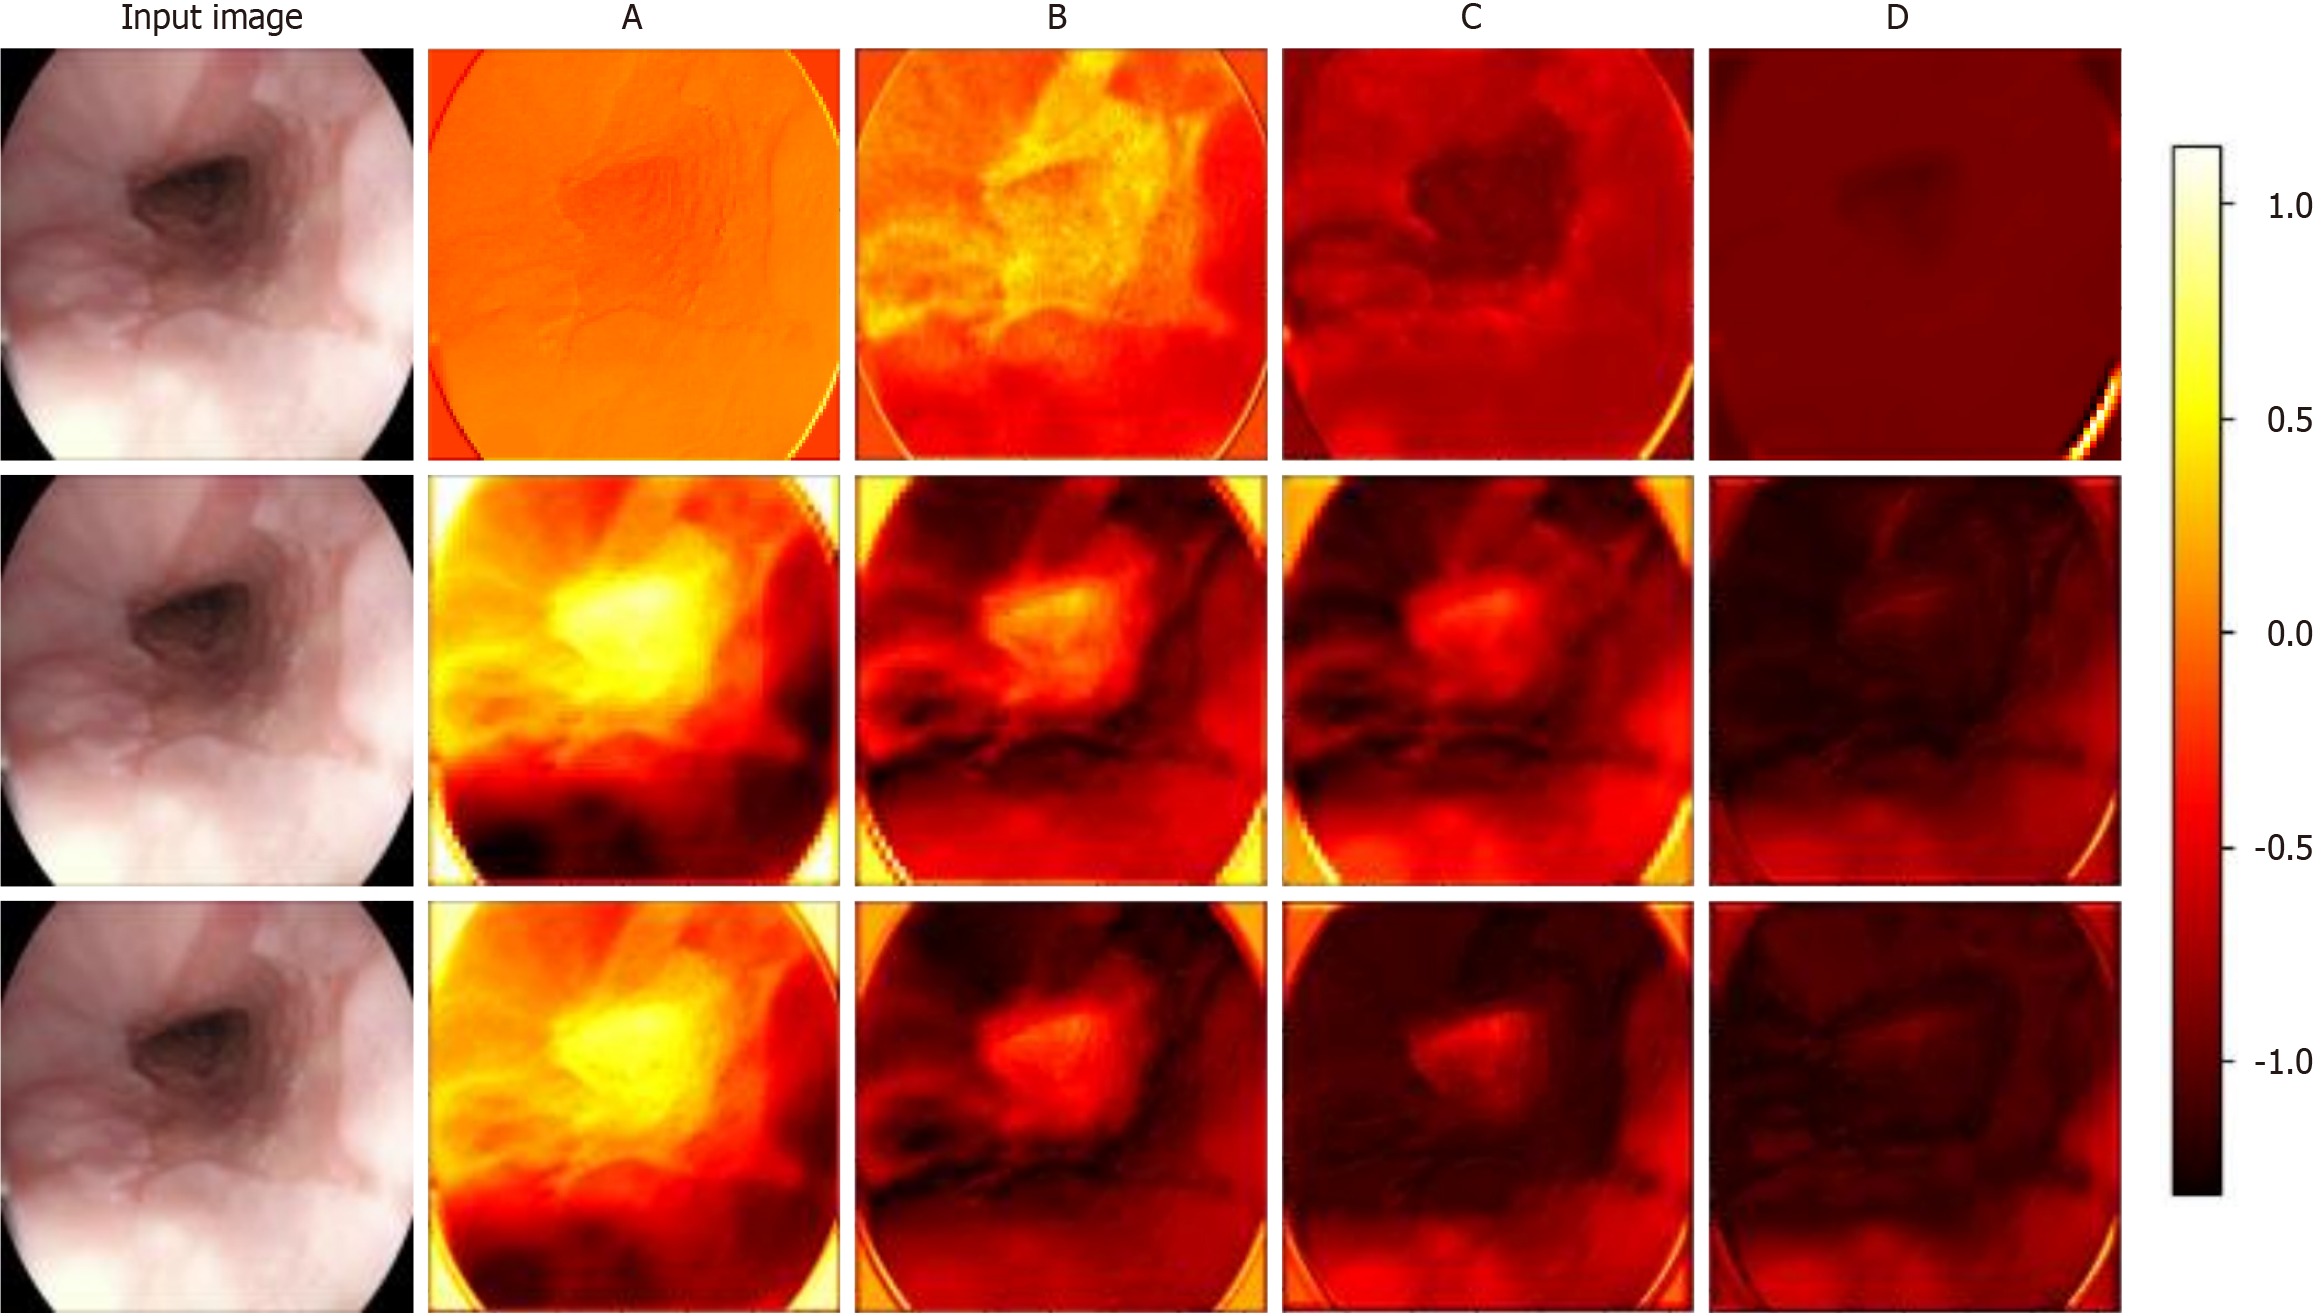

Visualizing the feature maps of each module in each model allows us to understand the internal mechanisms by which the models identify esophageal diseases. This is especially useful for examining the differences in feature extraction and semantic understanding across models. Figure 7 shows the results of visualizing different models for the identification of a particular case of esophagitis. This paper analyzes the differences in feature maps extracted by modules across four levels in ResNet, the transformer model, and Wave-ViT, with a focus on how Wave-ViT leverages frequency domain information to enhance its focus on disease regions in the esophagus.

By observing the intermediate feature maps extracted by each model, this study conducted a detailed analysis of the correlation between the model’s focus areas and pathological features[38]. ResNet primarily captures local details, such as the texture of the esophageal wall and the distribution of blood vessels. As the network depth increases, the model gradually learns higher-level features, such as the integrity of the esophageal mucosa and the shape and size of inflamed areas. However, ResNet mainly focuses on local spatial information within the image and has limited sensitivity to global information and different frequency components. The transformer model, on the other hand, captures relationships between different regions of the esophagus, such as the connection between inflamed areas and surrounding tissue. Due to its global perspective enabled by the self-attention mechanism, the transformer model is more effective than ResNet in identifying disease regions. Wave-ViT has the advantage of simultaneously capturing both local details and global contextual information in diseased regions. The wavelet transform highlights high-frequency details in diseased areas, such as irregular edges and abnormal textures. Additionally, the wavelet block extracts information at different scales from feature maps of various frequency components: High-frequency components highlight details within diseased areas, while low-frequency components capture global contextual information. As a result, the Wave-ViT model demonstrates a higher degree of focus on disease regions and achieves more precise localization of these areas.

In summary, the ResNet visualization results may indicate attention to the entire esophageal region but show a lower degree of focus on disease areas compared to the other two models. All three models’ shallow feature maps display local texture information, while deeper feature maps reveal more abstract regional features. However, both ResNet and transformer models lack emphasis on specific frequency domain information. Wave-ViT, in contrast, captures more frequency domain information, allowing it to extract richer semantic information from the esophagus, which explains why Wave-ViT demonstrates a higher focus on esophageal disease regions.